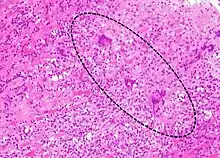

The gold standard is the biopsy of the myocardium, in general done in the setting of angiography. A small tissue sample of the endocardium and myocardium is taken and investigated. The cause of the myocarditis can be only identified by a biopsy. Endomyocardial biopsy samples are assessed for histopathology (how the tissue looks like under the microscope): myocardial interstitium may show abundant edema and inflammatory infiltrate, rich in lymphocytes and macrophages. Focal destruction of myocytes explains the myocardial pump failure.[10] In addition samples may be assessed with immunohistochemistry to determine which types of immune cells are involved in the reaction and how they are distributed. Furthermore, PCR and/or RT-PCR may be performed to identify particular viruses. Finally, further diagnostic methods like microRNA assays and gene-expression profile may be performed.